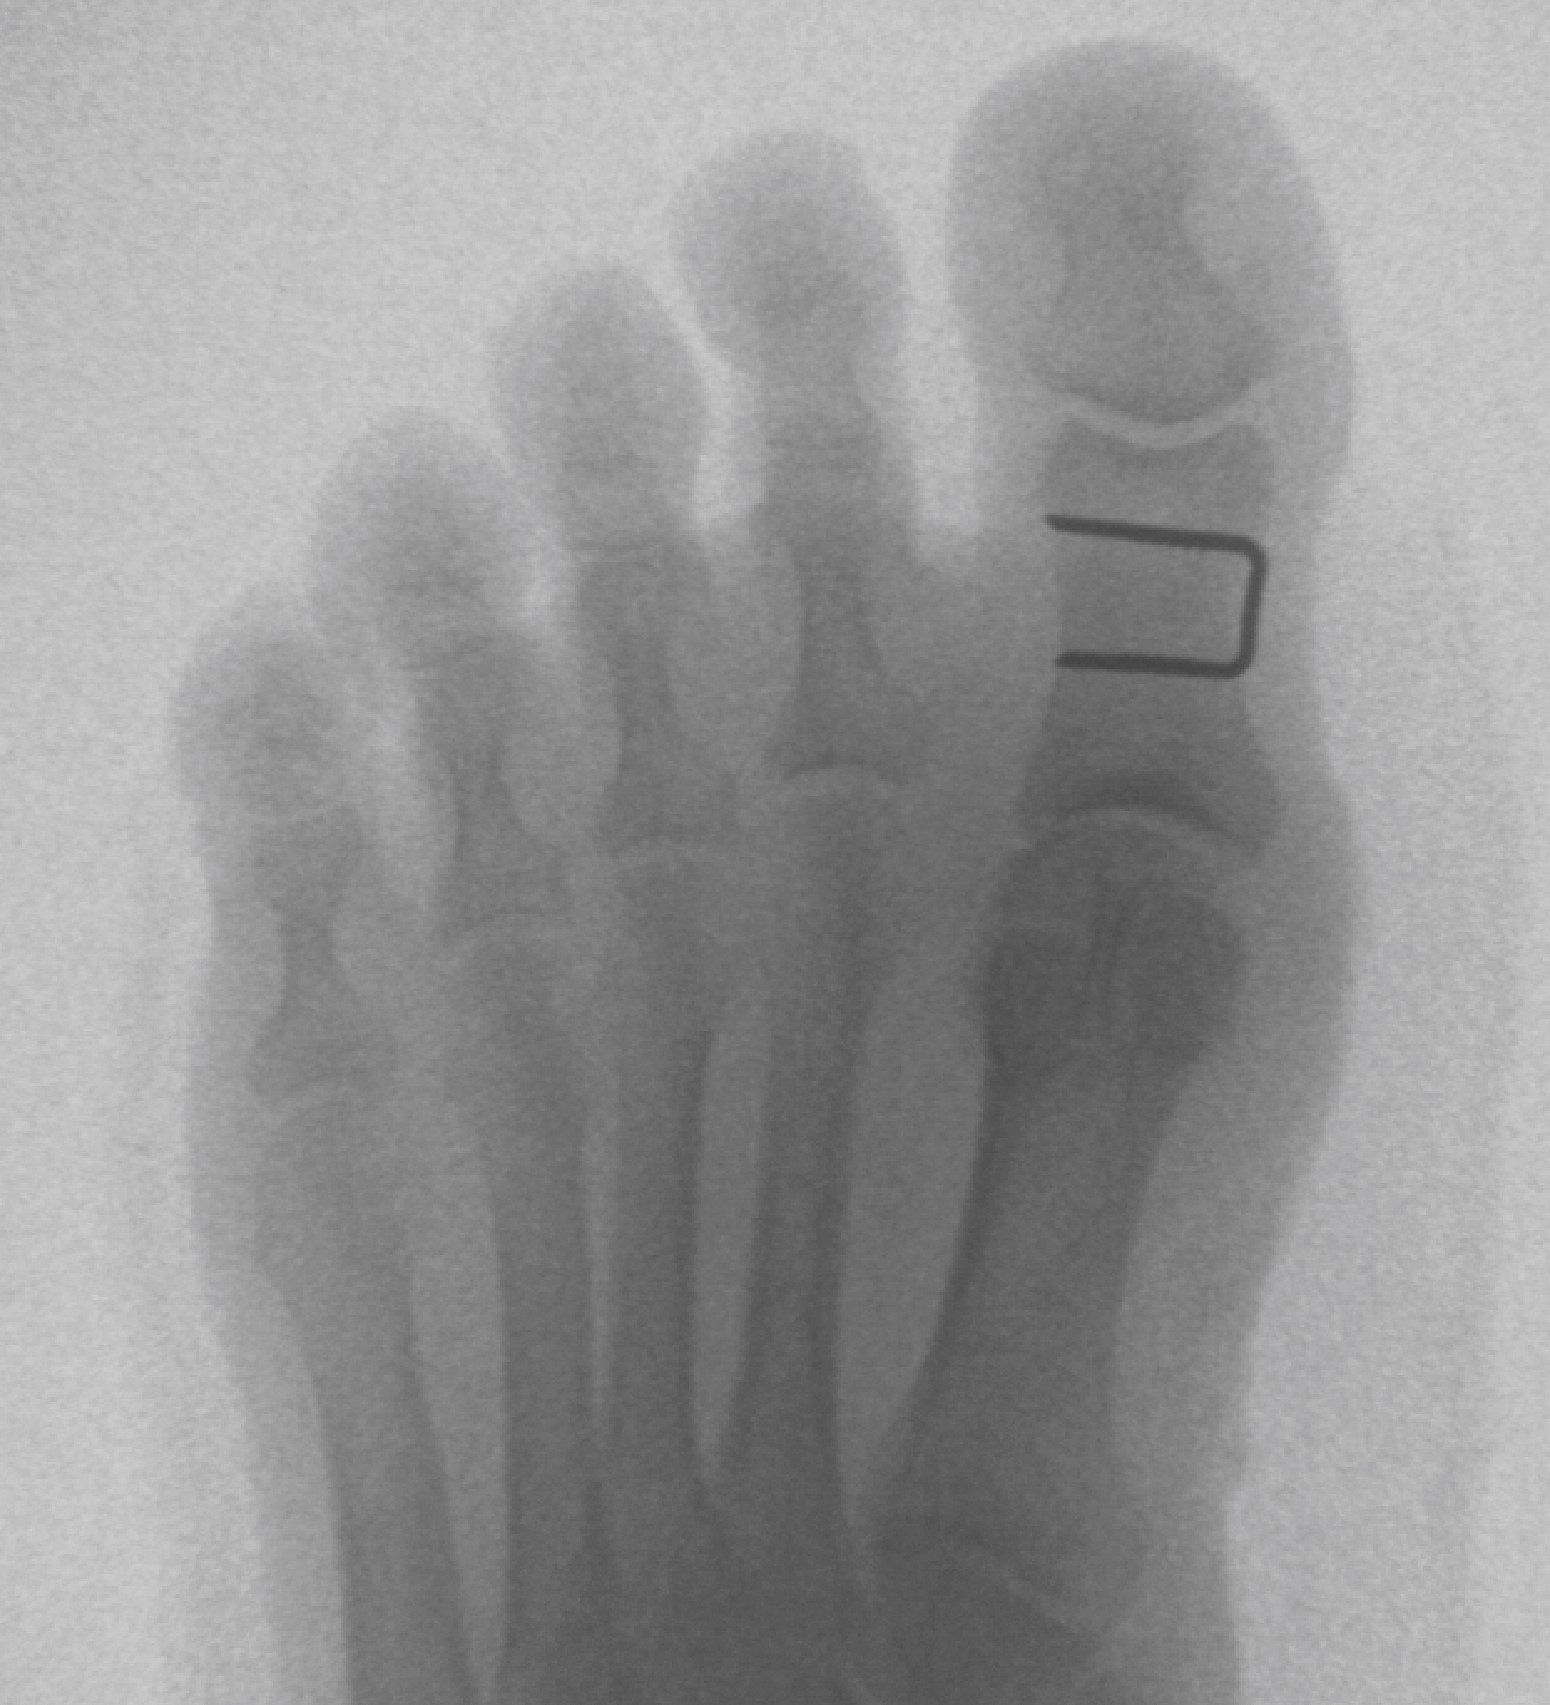

Home Schwerpunkte Krankheitsbilder Arthrose der Großzehe (Hallux Rigidus) Hallux Rigidus OP bei Arthrose der Großzehe: Youngswick Op und Akin OP

Hallux Rigidus OP bei Arthrose der Großzehe: Youngswick Op und Akin OP